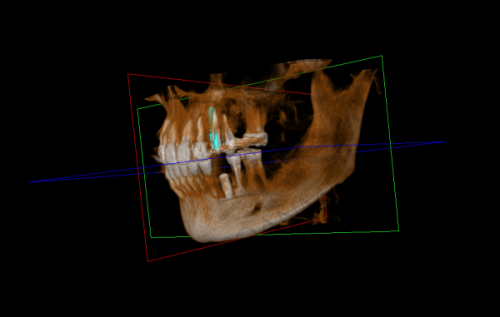

我见到了为我接诊的医生,他非常和蔼可亲,详细询问了我的牙齿情况和病史。然后,医生安排我做了一系列的检查,包括口腔X光片、CT扫描等。这些检查是为了全方面了解我的口腔状况,确定牙槽骨的密度、高度和宽度,以及是否存在其他口腔问题。检查过程中,医生和护士都特别细心,会提前跟我说明每个步骤,让我不会感到紧张。通过这些检查,医生制定了个性化的种植牙方案。

宿州康桥口腔医院的种植牙技术有特别多特色之处。首先,他们采用的是精良的种植系统,这些种植体的材质非常好,生物相容性高,能够与牙槽骨更好地结合,提高种植牙的成功几率。其次,医院拥有专精的医生团队,他们都有丰富的临床经验,能够根据患者的具体情况制定更适合的种植方案。而且,医院还引进了精良的数字化种植技术,通过计算机模拟种植过程,能够更精细地确定种植体的位置和角度,减少手术创伤,缩短手术时间。另外,医院的服务也非常贴心,从术前的询问、检查,到术中的治疗,再到术后的回访和维护,都有专人跟进,让患者感受到全方面的关怀。